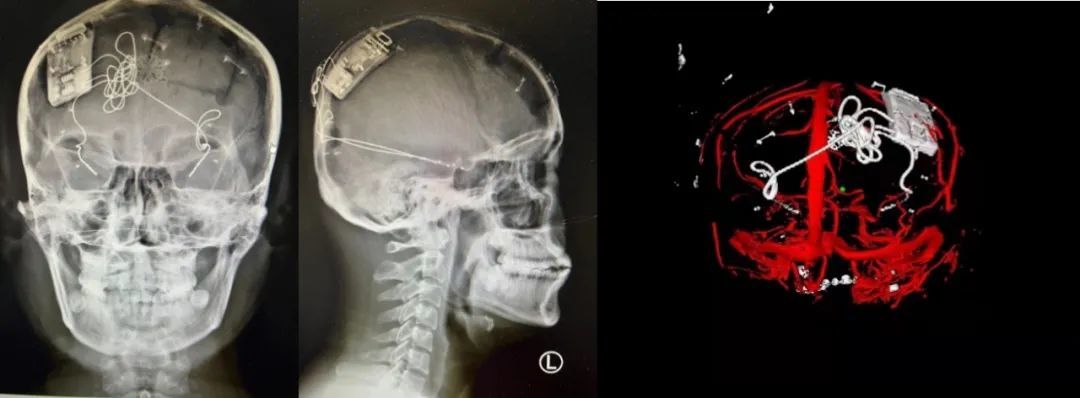

本次手術過程順利,術中刺激器各項指標均工作正常,術后重建顯示電極位置精準,腦電信號清晰?;颊邽槟行?,入院后診斷為雙側顳葉癲癇,此類癲癇為開顱手術的相對禁忌癥,在藥物無法控制的情況下,傳統(tǒng)治療效果欠佳 。

團隊根據(jù)術前計劃,在手術機器人輔助下完成雙海馬長軸電極及 IPG 植入,術后重建顯示電極位置精準,腦電信號清晰。術后第二天,患者即下床活動,身體狀況恢復良好。